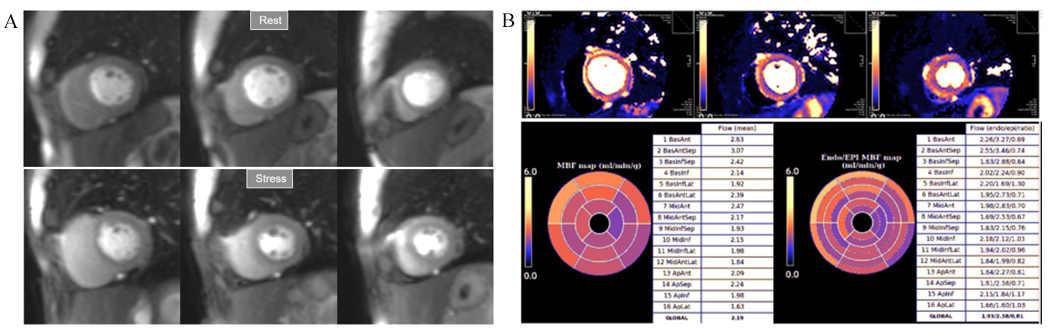

More recently, a new method has been proposed [56] that includes several important solutions contributing to a reliable implementation on the routine workflow of a CMR exam [57]. Firstly, it is based on a dual imaging sequence strategy (Fig. 24), where low-resolution blood pool images used for estimation of the AIF are followed by multi-slice 2D high-resolution myocardial perfusion sequence. The total duration of the scheme is around 500 msec, that allows for the obtention of 3 slices sampled every heart cycle, as long as the heart rate is below 120 b.p.m. AIF extraction from the low-resolution sequence has proven to be reliably obtained automatically [58] (Fig. 25). Second, motion and surface coil intensity correction are applied to both AIF and perfusion images [57, 59]. Third, a process of SI conversion into gadolinium concentration [Gd] units is performed for both sequences [56] (Fig. 26). Fourth, and most important, AIF [Gd] curve and perfusion [Gd] images are inputted into flow mapping step for pixel-wise myocardial flow mapping [57] rendering quantitative values of MBF (in mL/min/g) (Fig. 27). Based on a process of deep learning [60], myocardial segmentation and allocation of flow values are automatically processed (Fig. 28) and integrated into the MRI scanner using the Gadgetron streaming reconstruction software [61, 62]. The final output of the process consists on a bull’s-eye plot of color-encoded MBF values on the LV 16-segment model, and the listed numerical values of absolute flow at stress and at rest and, also, the derived MPR, each of them calculated for the endo- and epicardial halves of the segment (Fig. 29). The presence of inducible perfusion defects is thus detected not only visually on the perfusion color map, but also quantitatively estimated by the absolute values of stress MBF and the corresponding MPR of the involved myocardial segments (Fig. 30). Of note, in case of a suboptimal effect of the vasodilator agent, a lack of increase in stress MFB and MPR values is observed, leading to a potentially false positive diagnosis, in contrast with the visual assessment of perfusion, which, in this case, as stated above, would not show induced defects, with the potential for a false negative.

Fig. 32.Normal perfusion mapping. (A) Rest and stress perfusion studies showing absence of induced visual defect. (B) Normal global and segmental stress MBF.

Fig. 33.Mildly abnormal perfusion mapping. (A) Rest and stress perfusion studies showing absence of induced visual defect. (B) Mildly reduced global stress MBF (left table), particularly in the subendocardial regions (right table), suggesting MVD.

Fig. 34.Severely abnormal perfusion mapping. (A) Rest and stress perfusion studies in a patient with severe advanced multivessel CAD showing a global subendocardial and partially transmural inducible defect (arrows). (B) Perfusion mapping showing extremely reduced values of stress MBF indicating multivessel obstructive disease.